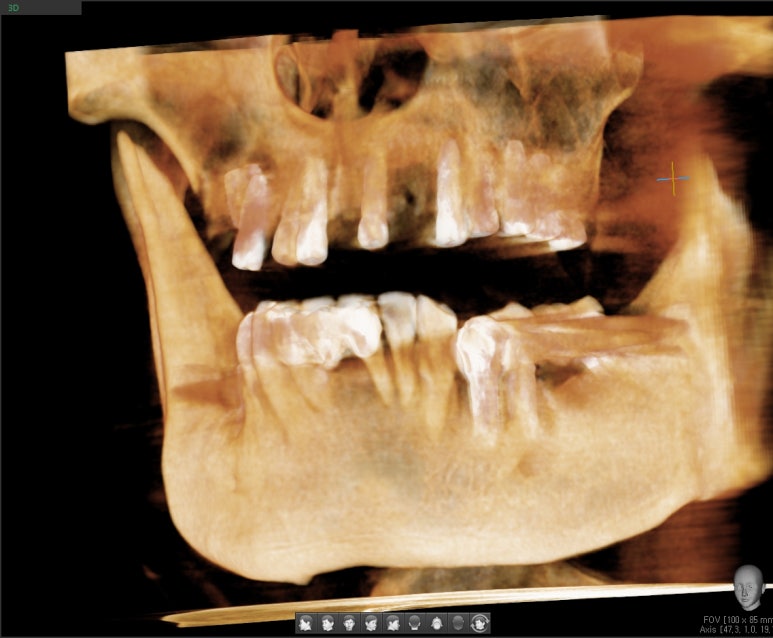

빨간선(상악동 하방), 파란선(치조골경계부위)

위의 엑스레이 사진에서 보듯이 상악동이라 불리는 공기주머니가 많이 내려와 있어서

그 부위에 어금니 임플란트를 심을 수 있는 뼈의 수직길이가 극히 적어서

일반 상악동 거상술보다 더 고난도의 상악동거상술 상악동 뼈이식까지 해야하는 상황이었습니다.

그리고 아래쪽에 어금니도 없는 부분도 어금니임플란트를 하기로 하였습니다.